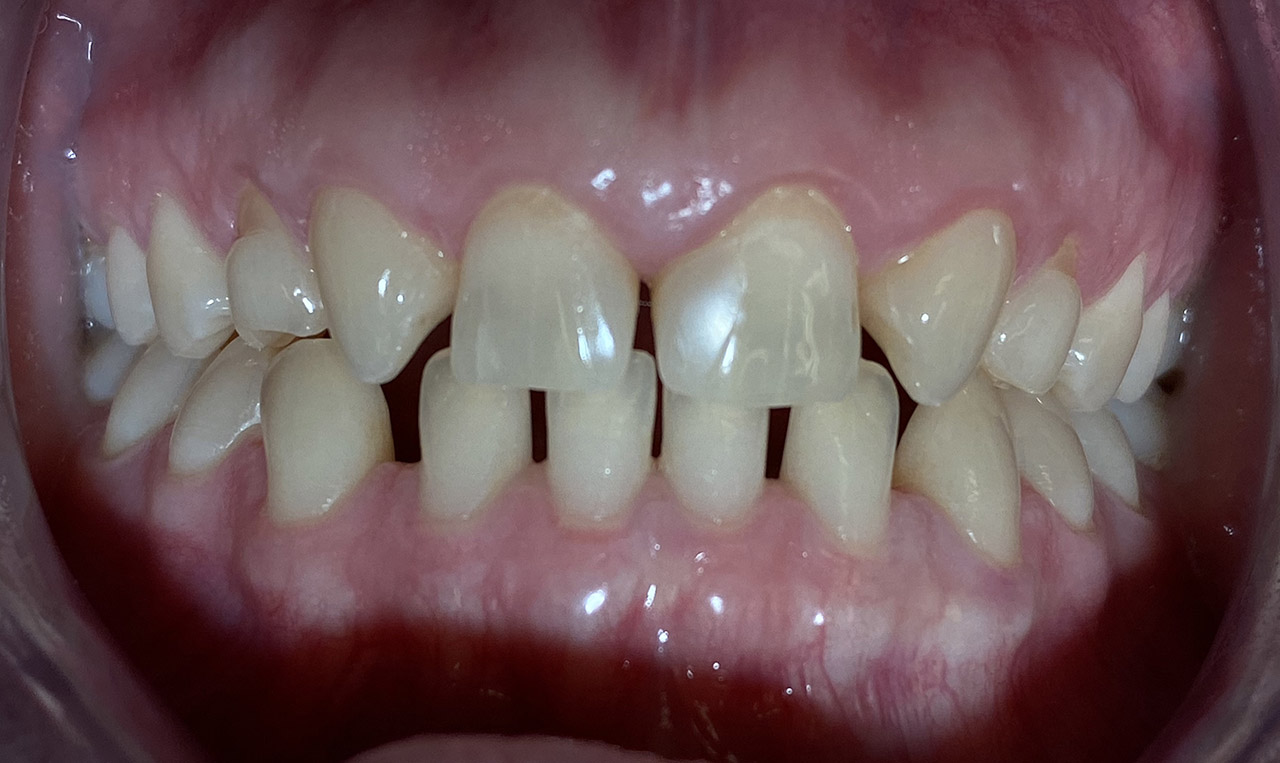

Aplasien/Nichtanlagen, dadurch bleibende Milchzähne, Diasteme/Zahnlücken,

Bleaching/Bleichen, Positionierung der Zähne/Kieferorthopädie (Dr. Maija Eltz), Verblendung mit Veneers/Keramikschalen.

Vorher Nachher